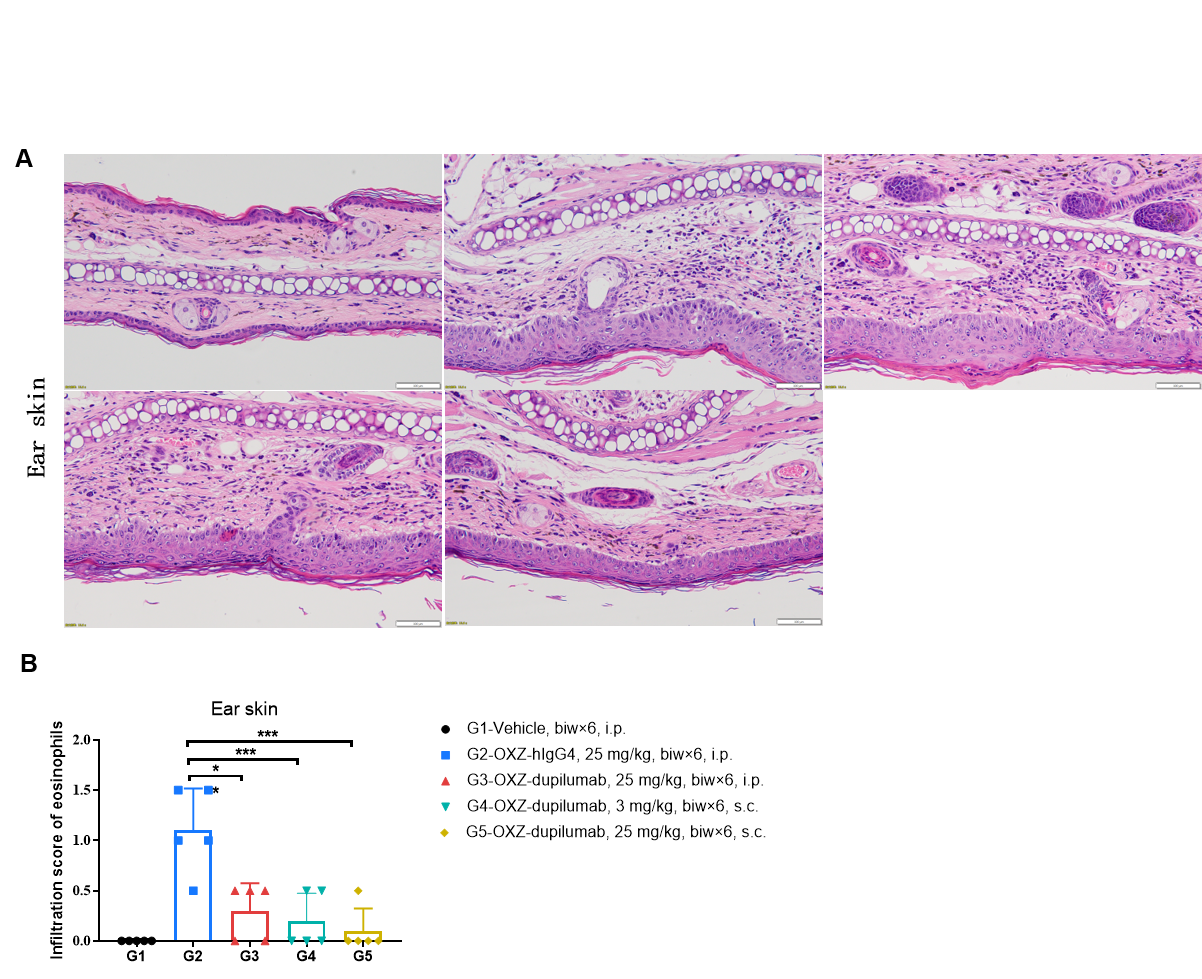

Effects of anti-human IL4RA antibody on inflammatory infiltration in ear skin of the AD mouse model. (A) Hematoxylin and eosin (H&E) staining. (B) Score of eosinophils infiltrated in ear epidermal skin (n=5). Infiltration scores of eosinophils in ear skin were significantly reduced after administration of the antibodies, demonstrating that the B-hIL4/hIL4RA mice provide a powerful preclinical model for in vivo evaluation of anti-human IL4RA antibodies. Infiltration score of eosinophils: 1=slight; 2=mild; 3=moderate; 4=severe. AD: Atopic dermatitis; ND: Not detectable.